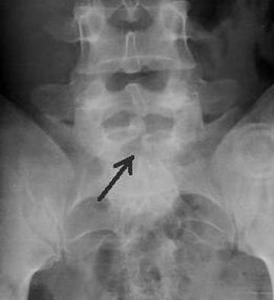

1.有骨梁存在,在X線片上可發現椎體背面有相應的骨質改變。